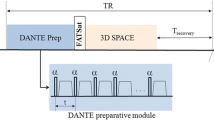

MR-DTI was performed using a 3D inversion-prepared fast gradient-echo acquisition with a water-selective excitation (1-2-1 binomial pulse sequence). The image volumes were acquired in coronal orientation and the image parameters were optimized by numerical simulation to ensure high signal from short-T1 thrombus while suppressing the signal from long-T1 blood [26]. The acquisition used centric k-space ordering, acquiring half the slice-encodes from each read-slice k-space plane per shot. The acquisition parameters were inversion time (TI) 340 ms, TE 6.3 ms, TR 12.2 ms, flip angle 25°, centric ordering, acquisition matrix 320 × 288 × 96, FoV 40 × 40 cm2, slice thickness 2 mm, 320 ms delay after each shot. Parallel imaging (ASSET) was used with an acceleration factor of 2. Zero-filling interpolation was used in-plane to give a reconstructed volume size of 512 × 512 × 96. The acquisition time was 5 min 59 s.